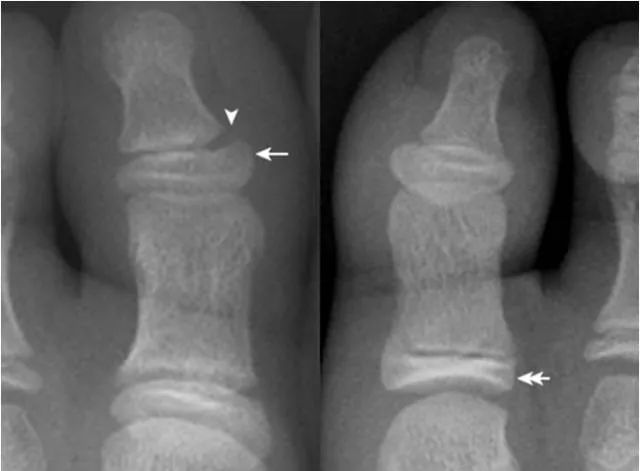

22.趾骨骨骺:

拇趾远节趾骨骨骺内侧较外侧宽(箭),其与趾骨干骺端间距离较宽(箭头),为正常表现,勿误认为是骺离骨折。近节趾骨骨骺可呈扁平状,并密度增高,亦为正常表现,勿误认为坏死。

23.锥状骨骺:

第2~4近节趾骨骨骺呈锥状(箭),多由生长紊乱引起,是一种变异。同时可见拇趾近节趾骨骨骺密度增高(箭头)。